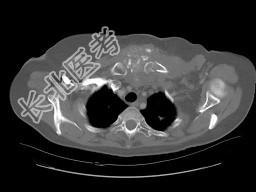

- 单项选择题女,46岁, 胸痛,乳腺癌放、化疗术后, 结合图像,最可能的诊断是 ( )

B、胸骨坏死